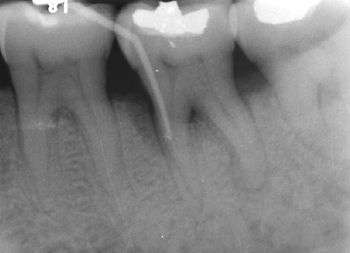

Furcation defect

In dentistry, a furcation defect is bone loss, usually a result of periodontal disease, affecting the base of the root trunk of a tooth where two or more roots meet (bifurcation or trifurcation). The extent and configuration of the defect are factors in both diagnosis and treatment planning.[1]

Because of its importance in the assessment of periodontal disease, a number of methods of classification have evolved to measure and record the severity of furcation involvement; most of the indices are based on horizontal measurements of attachment loss in the furcation.

In 1953, Irving Glickman graded furcation involvement into the following four classes:[3]

- Grade I - Incipient furcation involvement, with an associated periodontal pocket remaining coronal to the alveolar bone. The pocket primarily affects the soft tissue. Early bone loss may have occurred but is rarely evident radiographically.

- Grade II - There is a definite horizontal component to the bone loss between roots resulting in a probeable area, but sufficient bone still remains attached to the tooth (at the dome of the furcation) so that multiple areas of furcal bone loss, if present, do not communicate.

- Grade III - Bone is no longer attached to the furcation of the tooth, essentially resulting in a through-and-through tunnel. Because of an angle in this tunnel, however, the furcation may not be able to be probed in its entirety; if cumulative measurements from different sides equal or exceed the width of the tooth, however, a grade III defect may be assumed. In early grade III lesions, soft tissue may still occlude the furcation involvement, thus, making it difficult to detect.

- Grade IV - Essentially a super grade III lesion, grade IV describes a through-and-through lesion that has sustained enough bone loss to make it completely probeable.